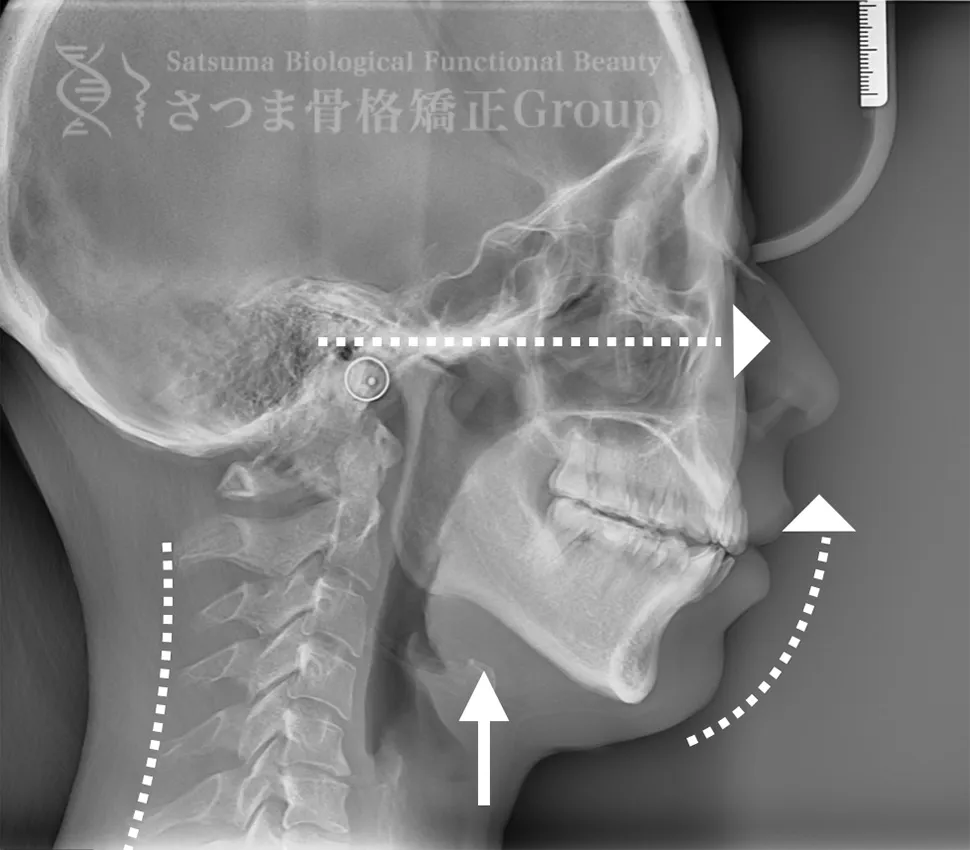

AFTER(マウスピース使用時)

整骨後、形成したマウスピースで形と顎関節の前方回転を誘導。上部頸椎のリリースを促進し、自家矯正力が働きやすいように誘導。蝶形骨口蓋縫合と蝶形骨上顎縫合をモビライゼーションし、可動をブーストし中顔面を短縮。

重度の肩凝りも軽減

After the osteopathy, the custom-formed mouthpiece guides the shape and promotes forward rotation of the temporomandibular joint.

It facilitates the release of the upper cervical spine and encourages the body’s natural self-correcting ability.

Mobilization of the sphenopalatine suture and the sphenomaxillary suture boosts mobility and shortens the midface.